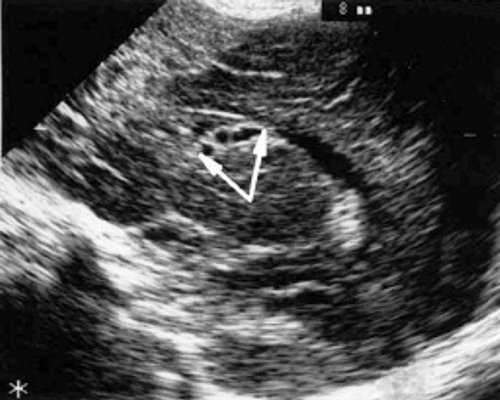

Рис. 2. Эхоэнцефалограмма ребенка Д. с цитомегаловирусной инфекцией, 2-е сут. жизни. Стрелками обозначены кисты в теле сосудистого сплетения левого бокового желудочка.

При эхоэнцефалографии у детей I группы выявлено от 1 до 3 изолированных кистозных структур (не сочетающихся с другими структурными изменениями) диаметром от 0,2-0,5 см (рис. 1, 2), расположенных в верхушке или теле сосудистого сплетения левого бокового желудочка. У 3-х из этих детей исходные данные вентрикулометрии соответствовали нормальным значениям. У 1-го ребенка отмечено незначительное (до 0,6 см) расширение межполушарной щели и субарахноидальных пространств по конвекситальной поверхности мозга и умеренное симметричное увеличение ширины лобных рогов (преимущественно) и высоты тел боковых желудочков (до 0,7 см).